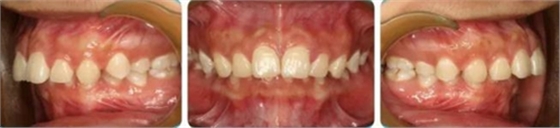

正面觀雙側(cè)面型基本對稱,側(cè)面觀上頜凸、下頜后縮,頦唇溝深。

恒牙列,上下牙列中線對齊,前牙深覆合、深覆蓋均為Ⅲ°。雙側(cè)磨牙、尖牙為Ⅱ類遠(yuǎn)中關(guān)系,A4C4、B4D4正鎖合。